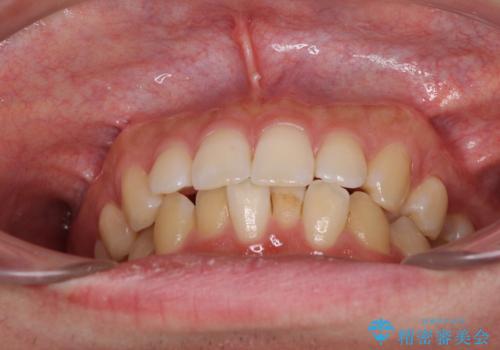

前歯のデコボコと突出感 インビザラインにて矯正治療

- 上下前歯のデコボコを気にして来院された患者様です。

インビザラインによる上下歯列の側方拡大と後方移動、IPR(歯と歯の間を削る)にるスペースの獲得により歯列を整えることとしました。

左上の小臼歯は捻転が強く、あえて180逆向きの状態で終了させる治療計画としました。